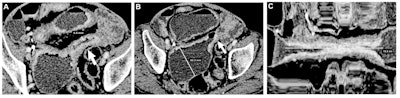

Contrast-enhanced CT enterography images of a Crohn's disease small bowel stricture in a 79-year-old male patient included in the study population. (A, B) Axial images show the presence of a long stricture (arrow) with a maximal stricture wall thickness of 6.8 mm (line in A) and marked maximal associated small bowel dilation (60.3 mm; line in B). (C) Curvilinear multiplanar reconstruction focused on the same small bowel stricture allows measurement of the total length of the stricture (10.2 cm). Images and caption courtesy of the RSNA.